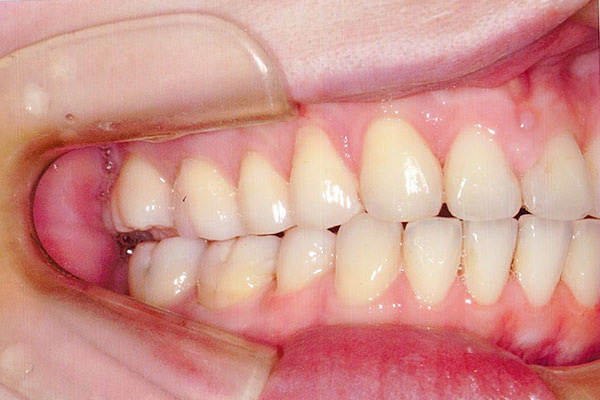

1年6ヶ月後